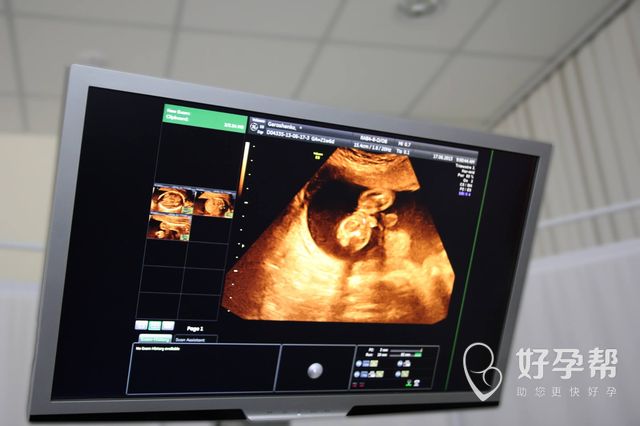

试管婴儿哪家医院好

如果要做试管婴儿的话,相信大家基本上也都希望能够选择一个技术最好的医院,试管婴儿哪家医院好?